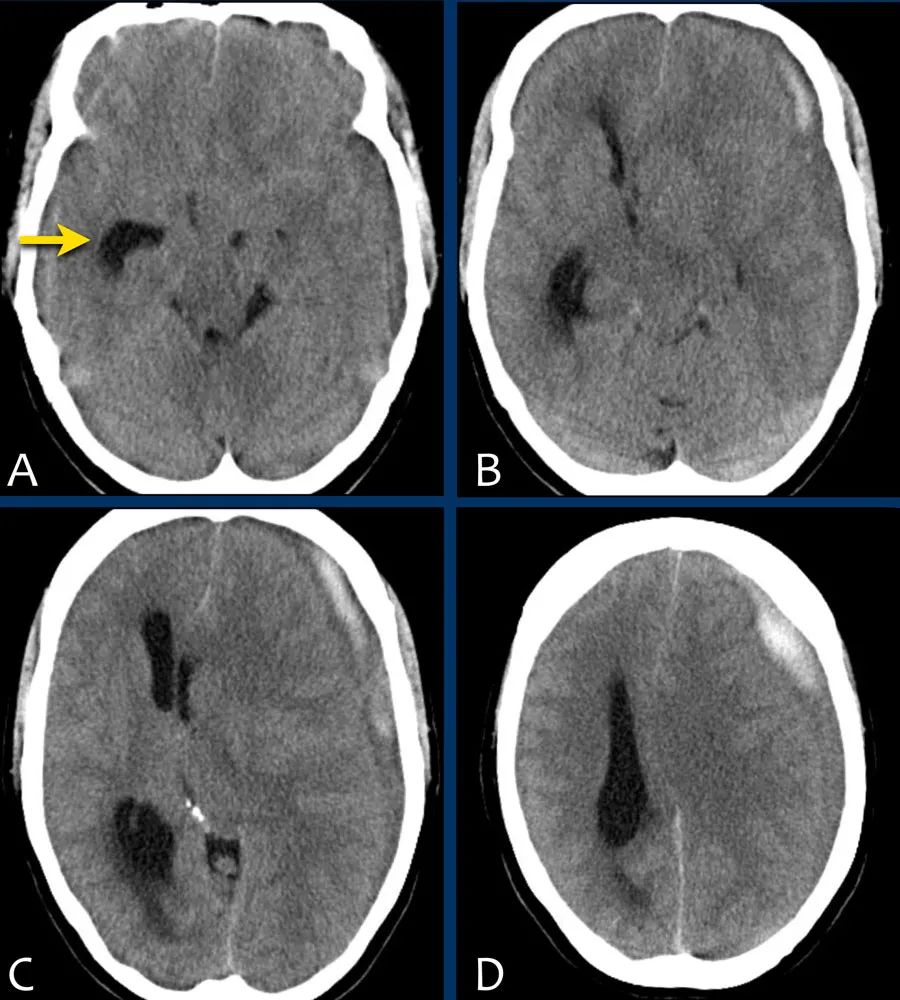

下图一例硬膜下血肿,很难发现(箭头)。

注意,在较高的水平上有双侧硬膜下血肿。

在罕见的情况下,急性硬膜下血肿可能与大脑等密度。

这种情况见于严重贫血、弥散性血管内凝血,或血肿被脑脊液稀释。

当一个慢性硬膜下血肿(>21天)变成低密度,可以和与脑脊液等密度,它可能模拟一个积液。

硬膜下血肿可沿大脑镰和小脑幕扩散,如本例所见。